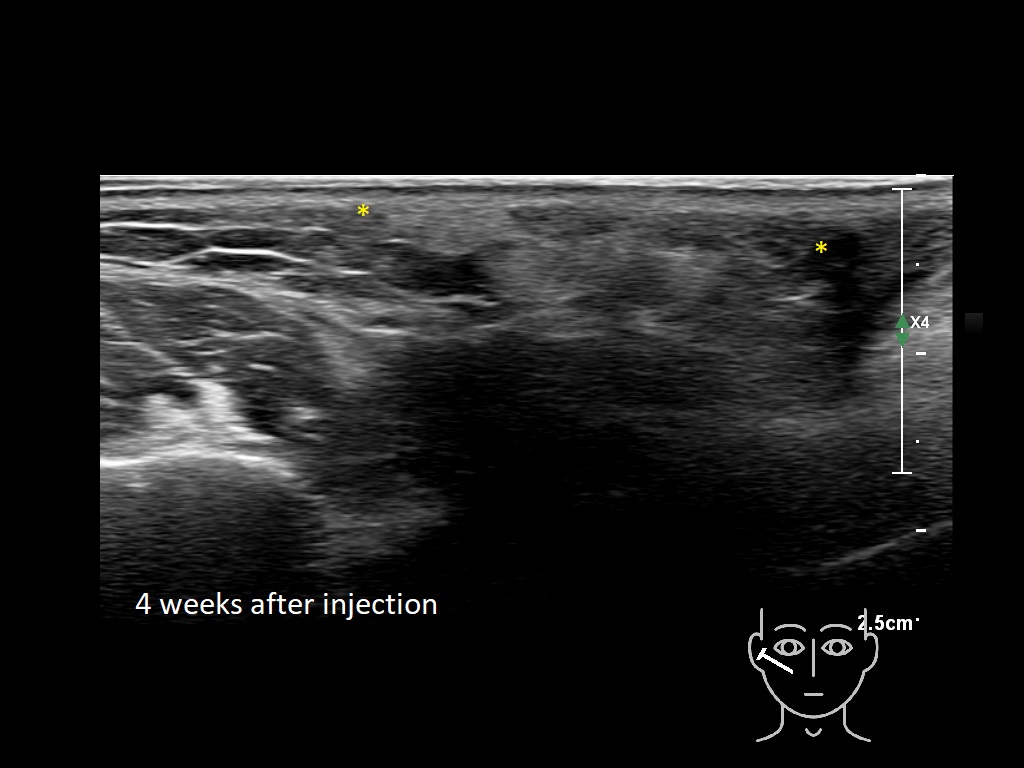

Draw in the image on the right where the fillers are located. To check if your answer is correct, please click on the secondary image.

Draw in the second image below where the fillers are located. To check if your answer is correct, swipe the first image to the right.